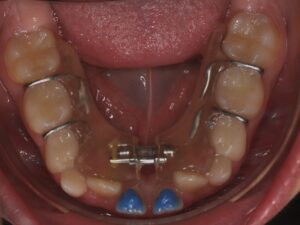

Il s’agit de l’orthodontie du jeune enfant. Elle permet d’intercepter un défaut de croissance ou d’éruption dentaire qui pourrait devenir irréversible s’il est pris en charge trop tard. De manière générale, il y a trois axes.

L'AXE DENTAIRE

Il correspond au maintien ou à la réouverture des espaces afin que les dents définitives puissent évoluer.

Les dents de lait sont souvent sous-estimées mais elles jouent un rôle primordial dans l’éruption des dents définitives. Il faut savoir que la nature n’aime pas le vide, une perte prématurée d’une « dent de lait » entrainerait un risque d’absence de place pour la « dent d’adulte ». Il peut donc être nécessaire de maintenir ou de rouvrir certains espaces.

Il s’agit de la mastication, la respiration, la posture linguale, les habitudes déformantes. Elles font partie intégrante de la bonne posture des mâchoires et des dents. Elles seront également contrôlées et interceptées. Les appareils sont nombreux en fonction de la malocclusion, ils peuvent être fixes ou amovibles. Très souvent, l’interception pourra être associée à un rendez-vous chez : l'ORL, l'orthophoniste, le kinésithérapeute ou encore l'osthéopathe.